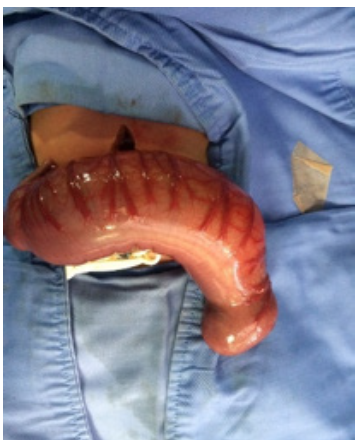

On admission at HOMI, the patient presented with markedly distended abdomen (Figure 1) with absent bowel sounds, normal position of the anus and no genital abnormalities.

Severe abdominal distension before surgery.

Figure 1: Severe abdominal distension before surgery.

Source: Own elaboration based on the data obtained in the study.